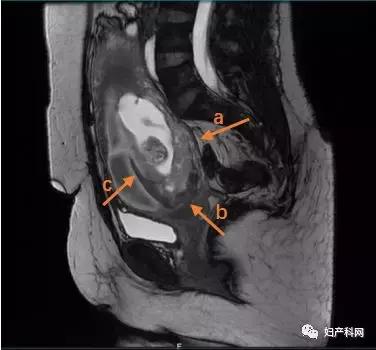

MRI检查:子宫增大,宫腔扩张,内见大量积血信号,孕囊位于后壁,胎盘位于后壁,与宫颈内口上方与宫壁分离,后壁胎盘附着处界限不清,部分呈齿状改变(图1)。诊断结果:考虑胎盘早剥伴植入,宫腔内大量积血。

图1,MRI检查:a.胎盘植入;b.胎盘覆盖宫颈内口;c.胎盘与子宫前壁剥离